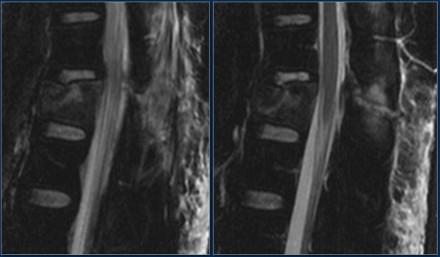

Look at the images.

What are the findings?

Then scroll to the next images.

The findings are:

- Vertebral bodies show marrow edema as a result of a fracture.

- Torn flaval ligament (yellow arrow).

- Fractures through the posterior elements (red arrows).

The TLICS-score is high, because there is distraction and injury to the PLC.